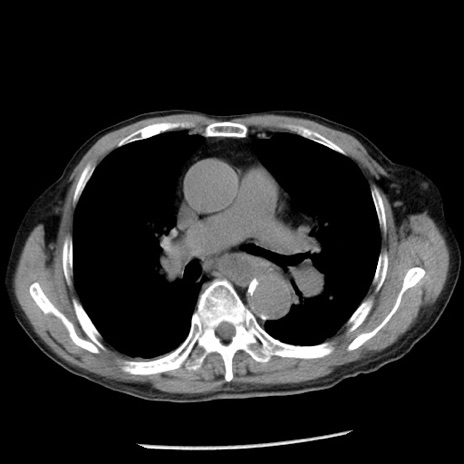

冠状断像

【症例】80歳代男性

【主訴】嘔吐

【現病歴】昨晩2回嘔吐あり、今朝になっても嘔吐あり。来院。

【既往歴】胃潰瘍

【身体所見】意識清明、BT 37.6℃、BP 166/95mmHg、HR 100bpm、SpO2 97%、腹部:平坦・軟、腸蠕動音聴取良好、圧痛なし。

【データ】WBC 21900、CRP 1.46